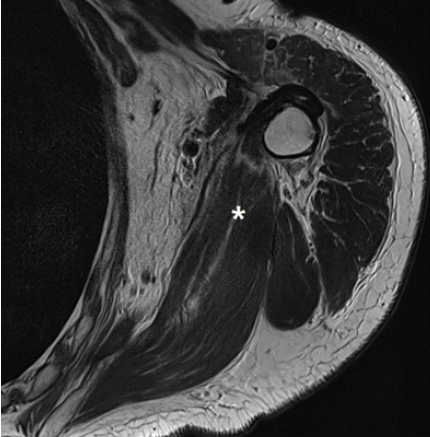

In all three patients, 2-year post-operative MRIs confirmed that the grafts remained intact without any retear (Fig. 5). There was no post-operative complication. All clinical outcomes were objectively assessed by a research coordinator who blinded the patient’s information and the details of this study.

Figure 5: Post-operative magnetic resonance imaging (MRI) of combined anterior latissimus dorsi and teres major tendon transfer of the left shoulder A post-operative T2-weighted oblique coronal image of the MRI shows the transferred tendons (asterisk).